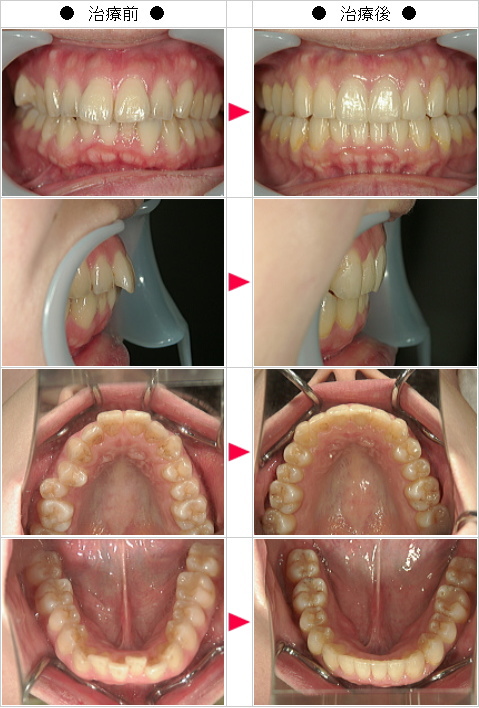

【インビザライン】出っ歯矯正の治療症例解説--全体矯正--

☆出っ歯矯正の治療症例[S・N様 40歳 女性]

-インビザライン・マウスピース矯正 治療症例解説